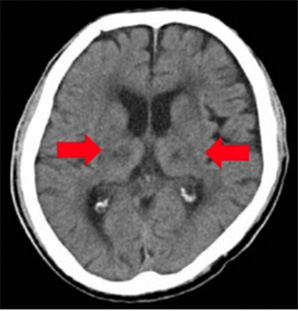

脳血管性認知症

VSRAD(ブイエスラド)

早期アルツハイマー型認知症診断支援システム

認知症を早期に画像で診断できます。